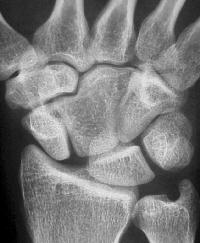

Clinical Example: Congenital capitate malformation with capitate trapezoid articulation and scapholunate diastasis

This patient was evaluated for wrist pain following a wrist sprain.

Plain films demonstrate an unusual capitate contour, articulating with the proximal trapezoid. There is a wide scapholunate interval.

The scapholunate angle is abnormal, about 80 degrees.

Radial and ulnar deviation views show minimal additional scapholunate widening in ulnar deviation.

The opposite wrist is similar. This anatomy probably represents congenital carpal coalition between the capitate and an os centrale.